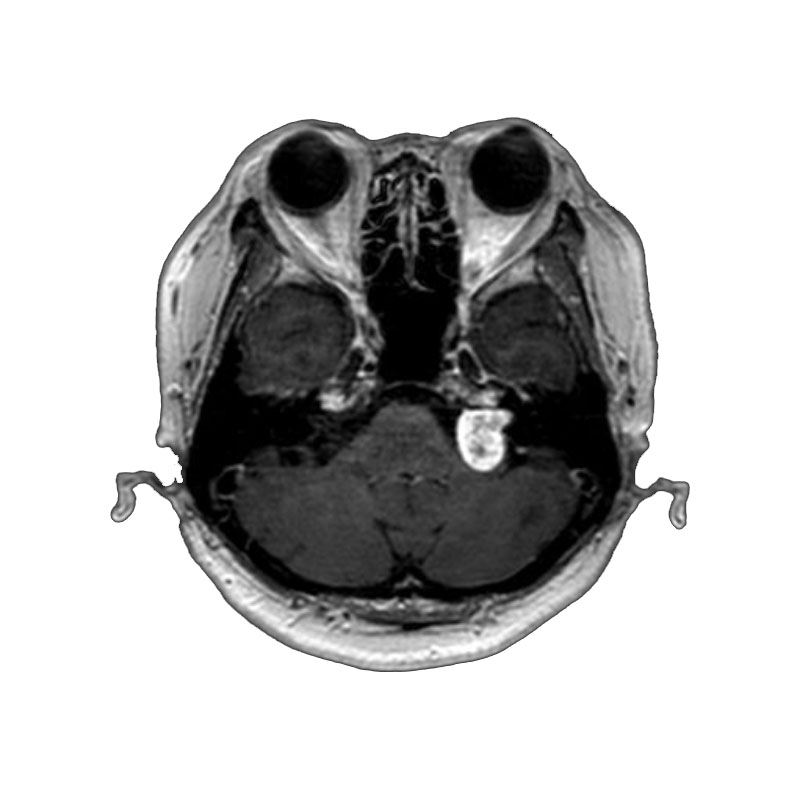

脳動静脈奇形

血管塞栓術

松田/濵田/元永